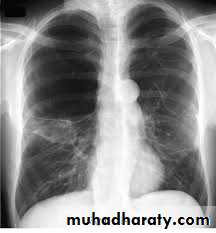

Radiology

Chest x-rayHyperlucency

Vascular attenuationHyperinflation (emphysema).

EmphysemaCT scan in Emphysema